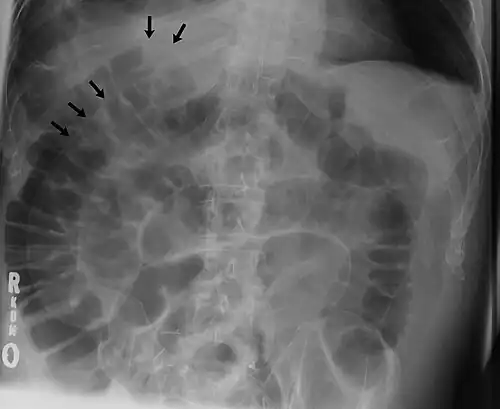

The double wall sign marks the presence of air on both sides of the intestine.[19] However, a false double wall sign can result from two loops of bowel being in contact with one another.[20] The sign is named after Leo George Rigler.[21] It is not the same as Rigler's triad.

Double wall sign. This is a secondary sign of pneumoperitoneum. Patient is supine, and air within the abdomen and lumen of the bowel accentuate both sides of the bowel wall. -